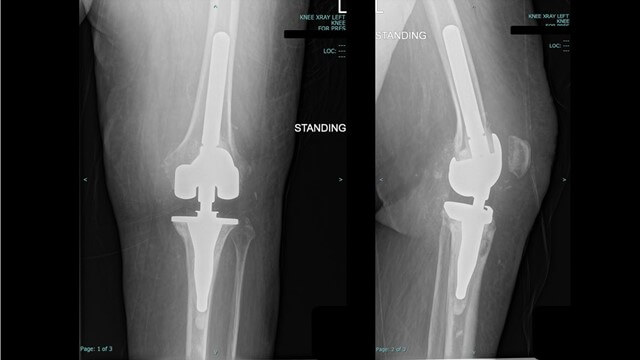

In the O.R., Dr. Greenberg and his team executed the preoperative plan with precision. The old and loose implants were removed, the bones were prepared, and the new hinged implant was securely placed. Incorporating the TraumaCad digital templating process for preoperative planning gave Dr. Greenberg both the confidence and satisfaction in knowing that the surgery would progress successfully and the outcomes would be desirable.

Dr. Greenberg’s patient experienced a quick and normal recovery without complications. She was discharged only two days after her surgery and follow-up X-Rays six weeks later revealed perfectly aligned implants. Today, the patient enjoys a pain-free existence and walks without issue: a testament to the success of her knee revision surgery.